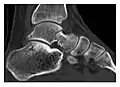

a

b

Figure 7: Fatigue fracture of the talus in a 25-year-old male basketball player with right hind foot and ankle pain, without history of trauma, and a normal initial radiograph (not shown). (a) One-month followup lateral radiograph shows normal appearance. (b) Sagittal T1-weighted MRI shows an irregular fracture line (arrow) within an ill-defined area of hypointensity corresponding to bone marrow edema.[1]